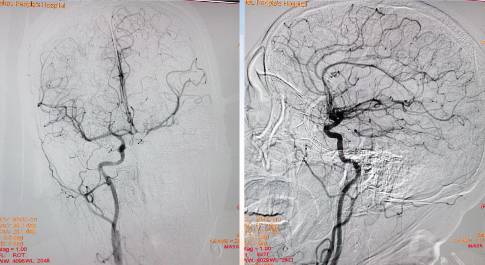

左侧椎动脉起始部成形

病历夹什么径技·第152期|串联营病历夹:川陕大营_https://www.jmylbn.com_新闻资讯_第21张

病历夹什么径技·第152期|串联营病历夹:川陕大营_https://www.jmylbn.com_新闻资讯_第22张

<<滑动查看下一张图片>>

确认血栓远近端

病历夹什么径技·第152期|串联营病历夹:川陕大营_https://www.jmylbn.com_新闻资讯_第23张

血管再通后造影

病历夹什么径技·第152期|串联营病历夹:川陕大营_https://www.jmylbn.com_新闻资讯_第24张

血管再通及左椎支架植入

病历夹什么径技·第152期|串联营病历夹:川陕大营_https://www.jmylbn.com_新闻资讯_第25张

病历夹什么径技·第152期|串联营病历夹:川陕大营_https://www.jmylbn.com_新闻资讯_第26张

病历夹什么径技·第152期|串联营病历夹:川陕大营_https://www.jmylbn.com_新闻资讯_第27张

左椎支架植入后造影

病历夹什么径技·第152期|串联营病历夹:川陕大营_https://www.jmylbn.com_新闻资讯_第28张